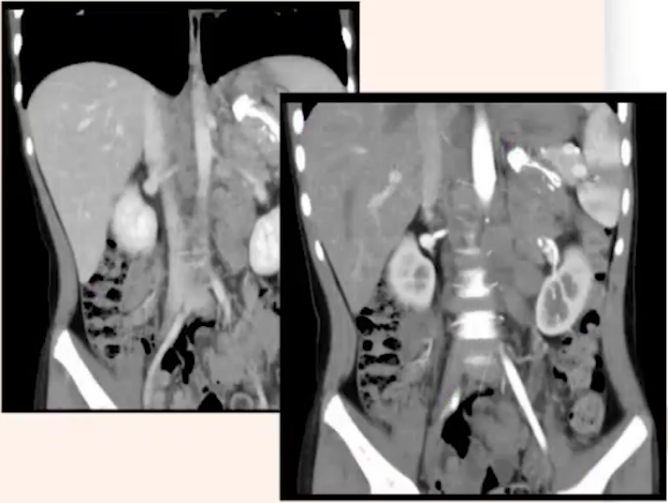

患者,女,7岁,因“持续性腹痛三日,伴腹部肿块发现一天”于2021年10月入院接受检查。初诊时,患者神志清晰,面色红润,未见水肿,浅表淋巴结无异常肿大,头颅形态正常,心肺功能检查未见明显异常。腹部平坦,无腹壁静脉曲张,触诊柔软,左上腹部有压痛感,但无反跳痛,未触及明显异常包块,肝脏与脾脏均未触及异常,Murphy氏征阴性,肾脏无叩击痛,无移动性浊音,肠鸣音正常,频率为4次/分,未闻及震水音或血管杂音。血常规检查结果显示,白细胞计数(WBC)为9.89×10^9/L,血红蛋白(Hb)为109g/L,血小板计数(PLT)为446×10^9/L,中性粒细胞计数(N)为7.28×10^9/L。生化及肿瘤标志物检测表明,患者肝肾功能基本正常,铁蛋白水平为58 ng/mL,乳酸脱氢酶(LDH)为505 U/L,神经元特异性烯醇化酶(NSE)为285.6 ng/mL,24小时香草基扁桃酸(VMA)排泄量为49.65 mg/24h。进一步进行双侧髂后上棘骨髓细胞学检查,结果提示存在瘤细胞骨髓转移,考虑神经母细胞瘤的可能性较大,占23%,且免疫表型中有59.81%的细胞表达GD2阳性。骨髓活检结果也支持神经母细胞瘤骨髓浸润的诊断。增强CT扫描显示,T10-L3椎体旁、左侧肾上腺区及腹主动脉旁可见一巨大软组织肿块影,大小约为5.4x4.2x9.0cm。肿块下内侧及腹膜后可见多发肿大、融合的淋巴结影,左肾静脉及左肾动脉被肿大的淋巴结包绕,导致左肾静脉显影不佳。此外,脊柱多发椎体骨质密度不均匀,胸腰段部分椎体形态异常。(见图1)综合上述检查结果,考虑患者为神经母细胞瘤并伴有淋巴结及骨转移的可能性较大。